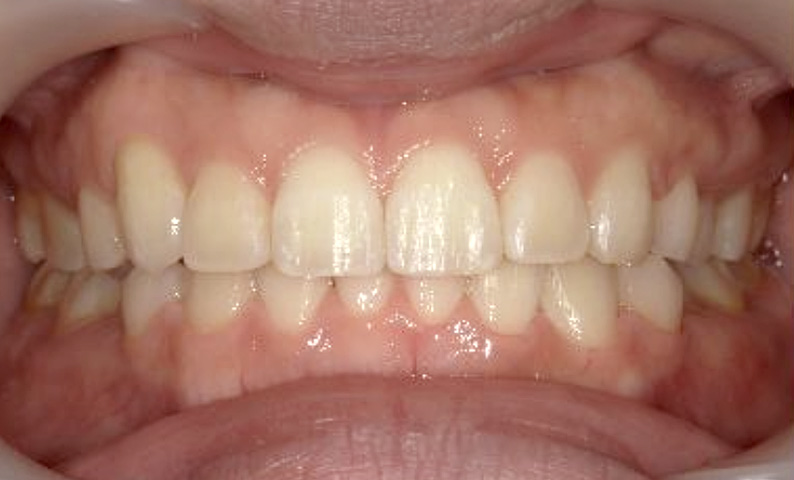

症例_001 下顎だけの部分矯正

治療期間:6ヶ月金額:27万円+税女性前歯のガタガタ下の前歯だけ

| Before | After |

|---|---|

|